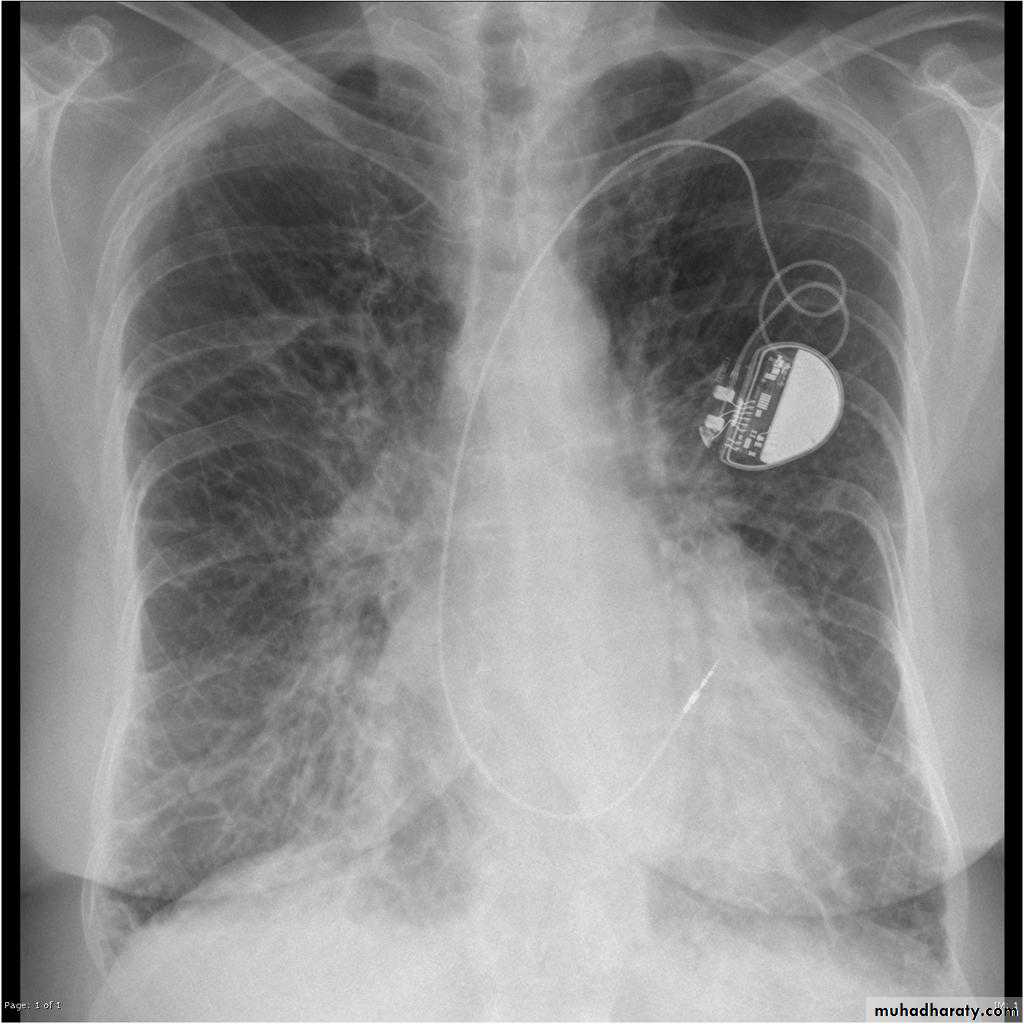

Pericardial effusions occur when fluid collects in the pericardial space (a normal pericardial sac contains approximately 30-50 mL of fluid).

Radiographic features

Plain radiographa very small pericardial effusion can be occult on plain film

there can be globular enlargement of the cardiac shadow giving a water bottle configuration known as Globe shape heart or pumpkin shape heart .

Pericardial effusion